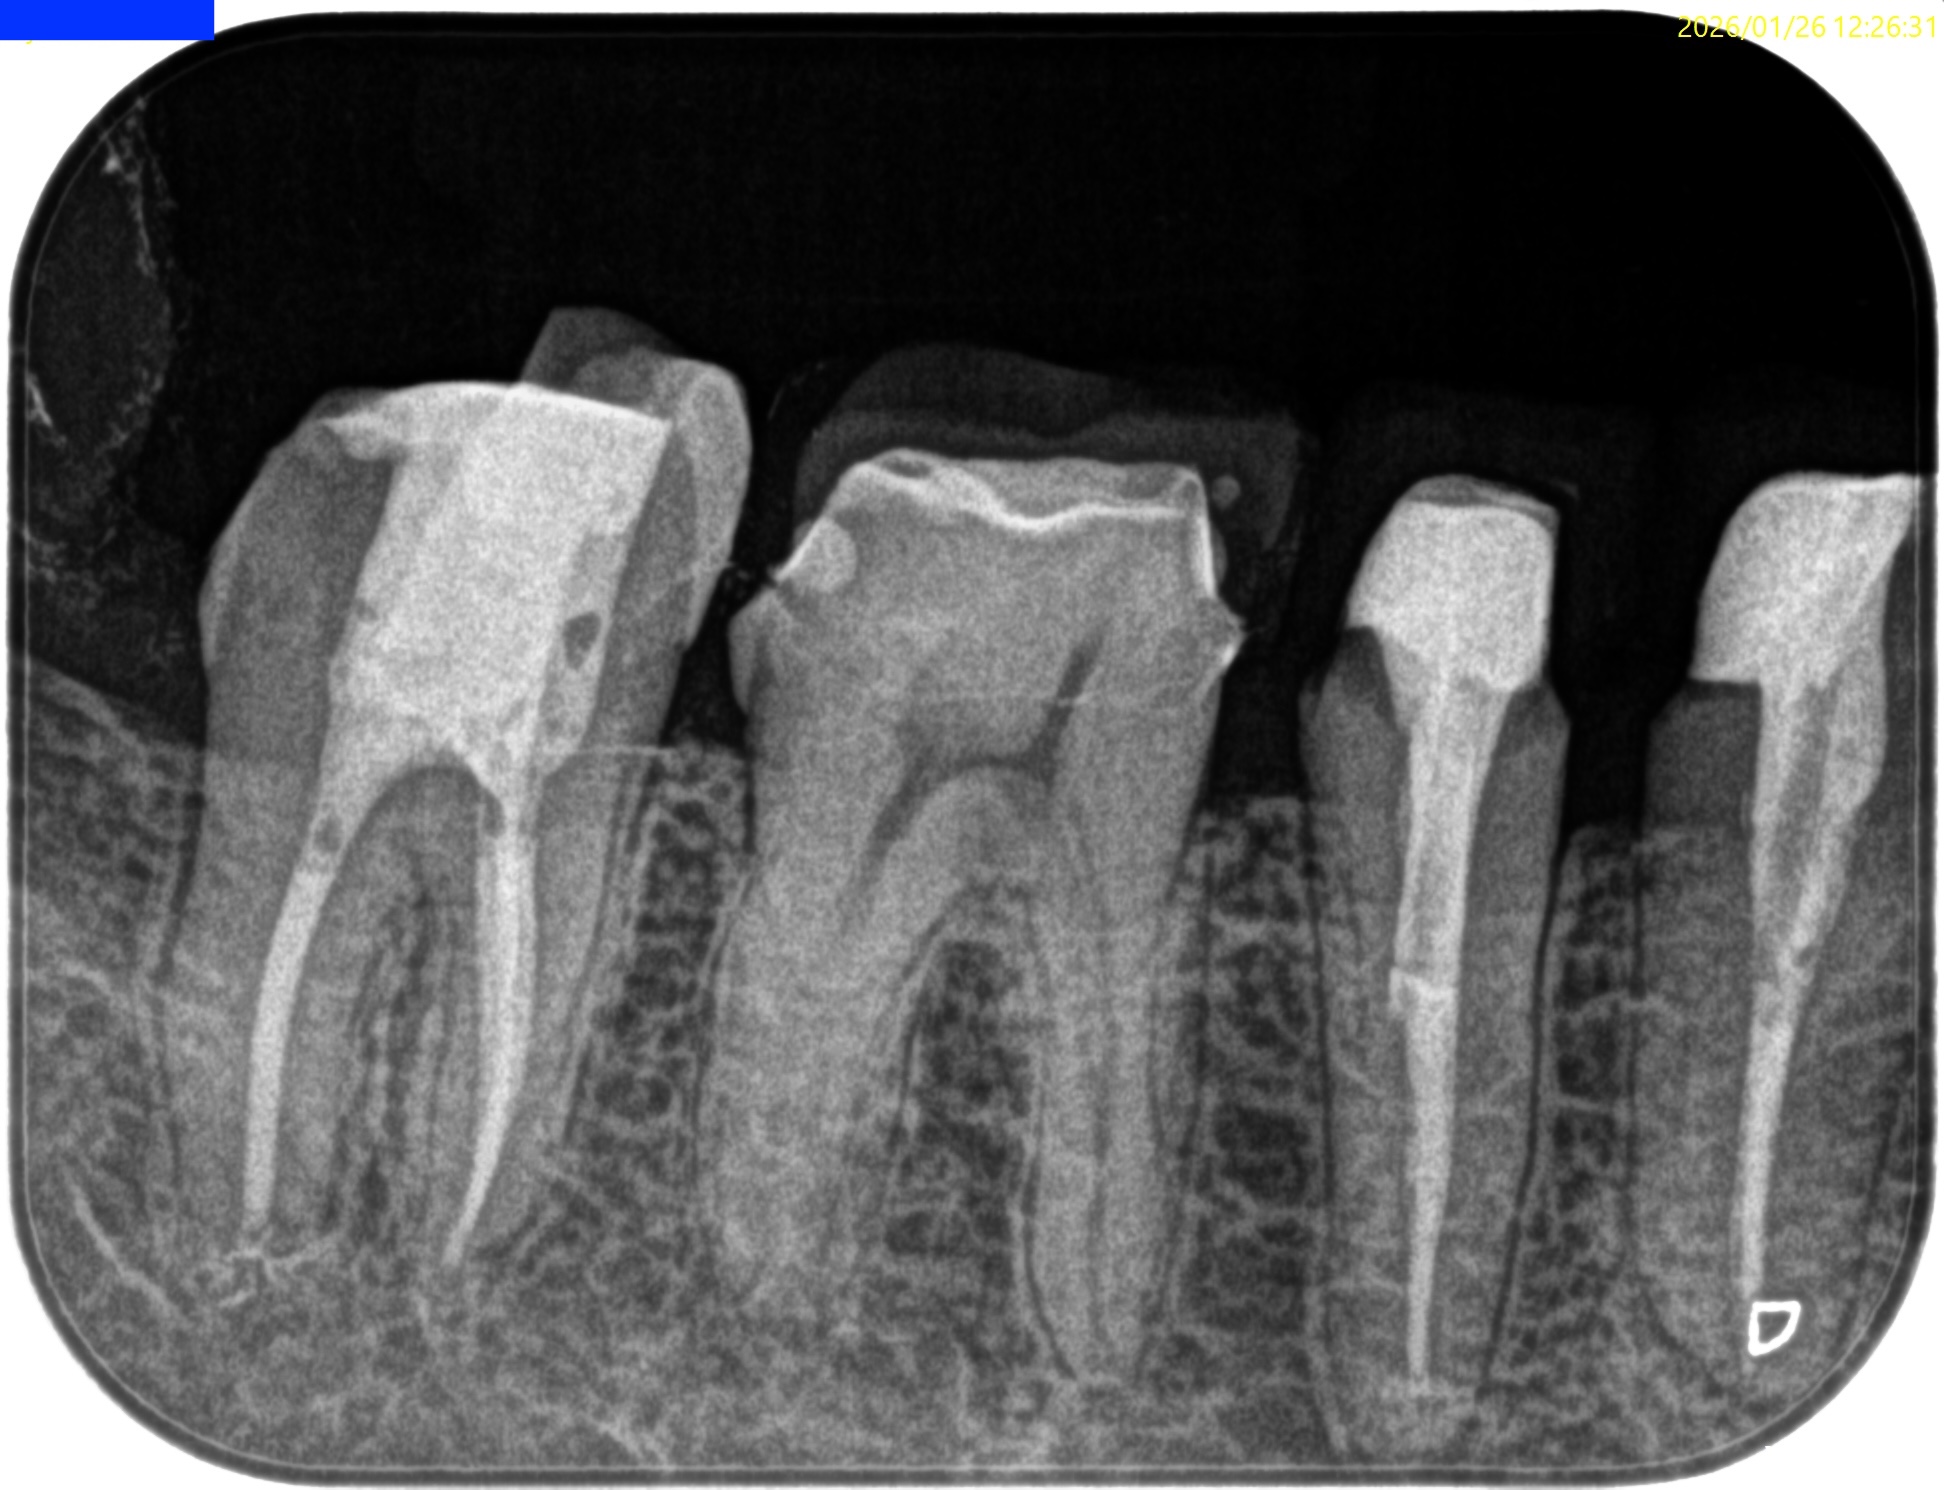

Pre-op Endo test(2026.1.26)

#31 Cold NR/20, Perc.(+), Palp.(-), BT(+), Perio Probe(WNL), Mobility(WNL)

#31 Dに直覆したような痕跡がある。

遠心根管だが、

遠心舌側は既に露髄しているだろう。

これが、痛みの原因だと思われる。

Pre-op Endo Diagnosis(2026.1.26)

Pulp Dx: Asymptomatic irreversible pulpitis

Periapical Dx: Normal apical tissues

Recommended Tx: RCT

術後にPA, CBCTを撮影した。